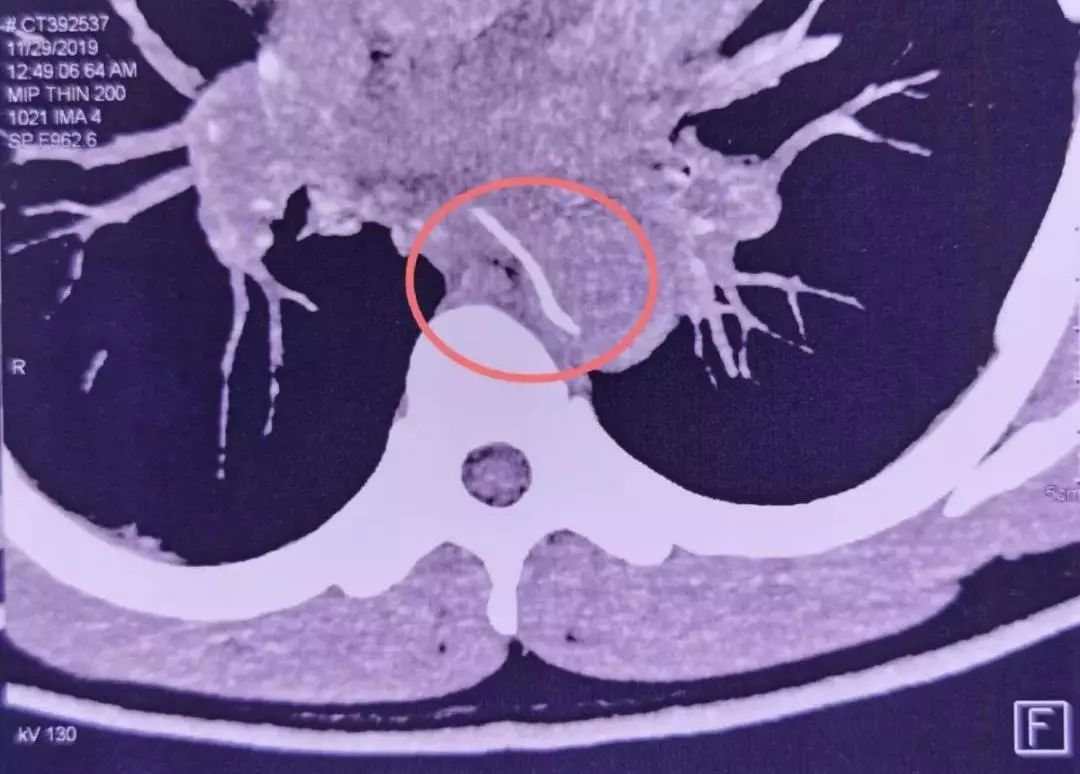

去医院CTA检查发现,一根鱼刺样的异物卡在了食管内,且已刺穿食管壁,一头已经扎进了胸主动脉。

11月29日,林先生来到了武汉大学人民医院急诊科就诊。魏捷教授检查发现,鱼刺像一把圆月弯刀,横插在食管和胸主动脉附近。如果盲目拔出,必定会形成主动脉破口,发生大出血。